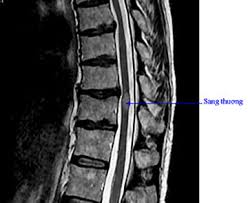

Click vào ảnh để xem 4 hình ảnh minh họa

Chụp ảnh cộng hưởng từ (MRI) hoặc chụp cắt lớp vi tính (CT): các xét nghiệm này tạo ra hình ảnh chi tiết bên trong cơ thể. Chúng sẽ cho bác sĩ xem liệu có điều gì khác đang ảnh hưởng đến thần kinh, như khối u, trượt đĩa đệm hoặc thu hẹp tủy sống.